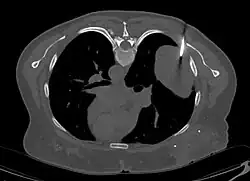

En tomodensitométrie[20],[31], quelle que soit la localisation, une tumeur fibreuse solitaire apparaît comme une masse tissulaire ovoïde ou lobulée, bien délimitée, refoulant les structures voisines sans les envahir. Elle se rehausse fortement après injection de produit de contraste. Les tumeurs de petite taille sont homogènes, mais les plus volumineuses présentent des plages hétérogènes de nécrose et d'hémorragie intra-tumorale. Il n'y a pas habituellement de calcifications et, lorsqu'elles sont présentes, elles sont de petite taille[31]. Les tumeurs malignes peuvent se présenter accompagnées de nodules pulmonaires métastatiques, et tendent à être plus volumineuses et plus hétérogènes[42].

- Tumeur fibreuse solitaire du rétropéritoine

Aspect tomodensitométrique, sans (A) puis avec (B) injection de produit de contraste[44].